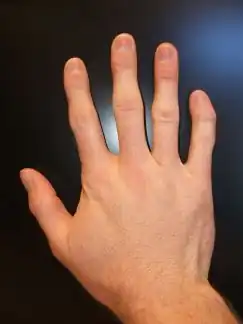

Andersen–Tawil syndrome affects the heart by prolonging the QT interval, a measure of how long it takes the heart to relax after each heart beat. This, as in other forms of long QT syndrome, can lead to abnormal heart rhythms such as ventricular ectopy or ventricular tachycardia causing palpitations.[6] The ventricular tachycardia seen in Andersen–Tawil syndrome often takes a form known as bidirectional ventricular tachycardia. The arrhythmias seen in association with the condition can cause sudden cardiac death, but the risk of this is lower than in other forms of long QT syndrome.[1] The physical abnormalities associated with Andersen–Tawil syndrome typically affect the head, face, limbs and spine. Abnormalities of the head and face include an unusually small lower jaw (micrognathia), low-set ears, widely spaced eyes (hypertelorism), a broad forehead and nasal root, a high arched or cleft palate, and a long narrow head (scaphocephaly).[4] Abnormalities of the limbs and spine include an abnormal curvature of the fingers, particularly the fifth finger (clinodactyly), fused fingers or toes (syndactyly), short stature, and a curved spine (scoliosis).[4]

Clinodactyly – abnormal curvature of 5th finger towards 4th finger

Clinodactyly – abnormal curvature of 5th finger towards 4th finger -